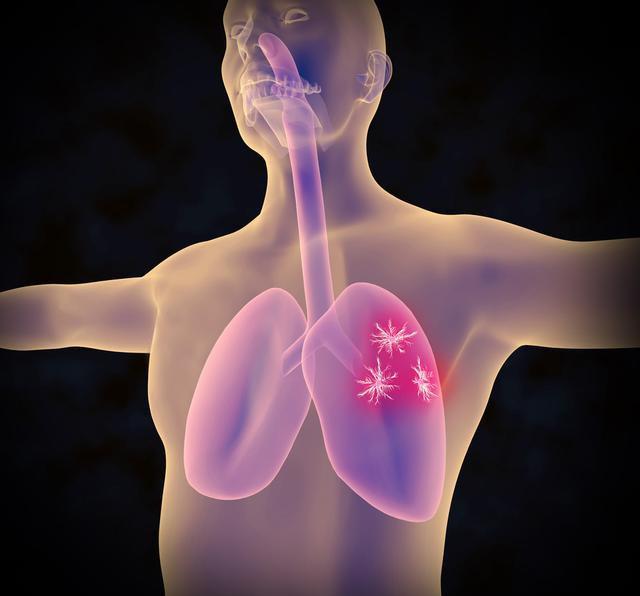

2.哪些磨玻璃结节可能是肺癌?

>20 mm的磨玻璃结节恶性率有80%;CT上结节表现为分叶征、毛刺征、胸膜凹陷、部分实性;贴近脏层胸膜的周围型磨玻璃结节。还有一些磨玻璃结节动态观察发现结节增大或者实性成分增加也要警惕恶性可能。